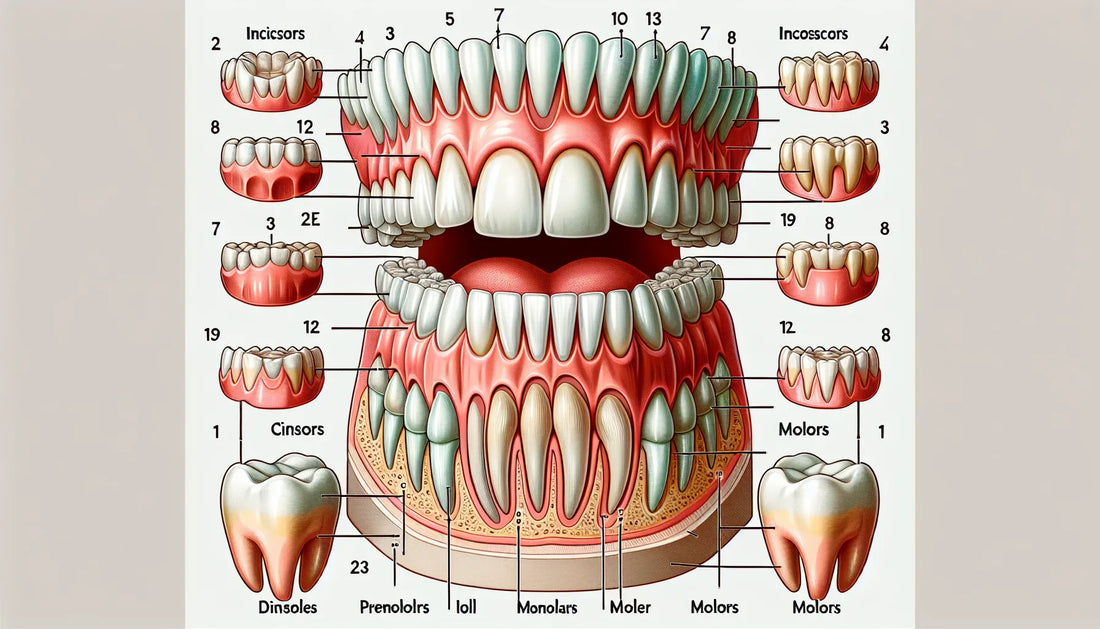

As children grow, their baby teeth begin to loosen and fall out—a process that usually starts around age six and continues into early adolescence. This makes way for the permanent teeth, which include a few additions to the lineup. Adults have 32 teeth in total, which include:

8 Incisors: The sharp, chisel-shaped front teeth used for cutting food.

4 Canines: Pointed teeth next to the incisors used for tearing food.

8 Premolars: Teeth between the canines and molars used for crushing and grinding.

12 Molars: Including four wisdom teeth, these are used for grinding food and are the last to emerge, typically in late adolescence or early adulthood.